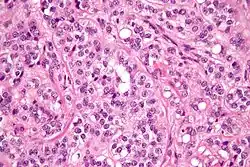

| Micrograph of a Sertoli cell tumour. H&E stain. | |

A Sertoli cell tumour, also Sertoli cell tumor (US spelling), is a sex cord–gonadal stromal tumour of Sertoli cells. They can occur in the testis or ovary. They are very rare and generally peak between the ages of 35 and 50. They are typically well-differentiated and may be misdiagnosed as seminomas as they often appear very similar.[1]

Microscopy and immunohistochemistry are the only way to give a definitive diagnosis, especially when there is a suspected seminoma.[3]